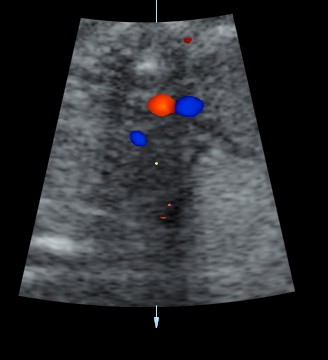

double vessel sign seen in front of spine

double vessel sign seen behind the heart

1. double vessel sign of aorta and azygos vein running side by side , with azygos slightly posterior,